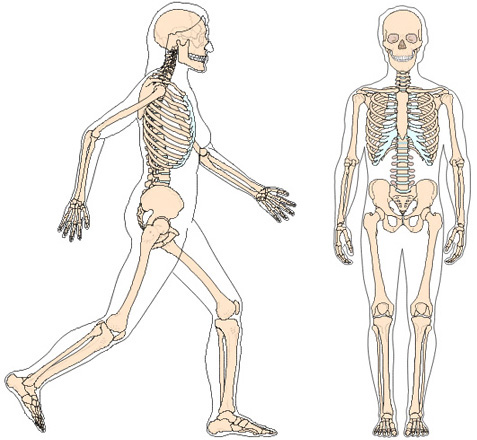

Der Körper besteht aus drei Hauptteilen:

Becken als Mittelebene, Oberkörper wird auf die Mittelebene abgestützt, die Beine mit den Füssen werden am Becken aufgehängt.

Ist die Mittelebene nicht waagrecht und senkrecht in der Mitte ausgerichtet, kann weder der Oberkörper noch die Beine ausgeglichen abgestützt oder aufgehängt werden.

7. Zum Unterschied der heutigen Messmethoden, die sich aufs Skelett beziehen: Knochen, Gelenke und Wirbelkörper |

8. Das heisst: Für die Bewegung benötigt es die Muskelkraft. Für die Kraftoptimierung benötigen die Muskeln die Skelett-Knochen. Sind laut Statik die Kräfte im ruhenden Zustand nicht ausgeglichen, verformt des den Körper, indem es ihn komprimiert verzieht und verdreht. |

Kann sich ein Skelett selbständig bewegen?

Im Wissen, das sich kein Skelett aus eigenem Antrieb bewegen kann. Für den Zusammenhalt der Knochen, Gelenke, Wirbelkörper und die Bewegung sind die Muskeln, Sehnen und Bänder verantwortlich.

Skelett

Das Skelett besteht aus einzelnen Knochen, Gelenken, Wirbelkörpern und wird über Bänder, Sehnen und Muskeln zusammengehalten und bewegt. (ca. 206 Knochen im erwachsenen Alter)

Muskulatur / Sehnen und Bänder

Muskulatur, Sehnen und Bänder sind für die Bewegung und den Zusammenhalt des Skeletts verantwortlich. Die Muskeln benötigen die Knochen als Kraftübersetzung. (ein gesunder Mensch ca. 656 Muskeln)

Zusammengefasst besteht das Skelett aus drei Teilen, der Mittelebene dem Becken, abgestützt darauf der Oberkörper und am Becken angehängt die Beine mit den Füssen. Über eine schiefe Beckenebene verändert sich automatisch die Oberkörperhaltung. Diese Fehlkräfte wirken wiederum auf das Becken und dadurch auch auf die Bein- und Fussstellungen, die diese Fehlbelastungen auf den Boden übertragen.